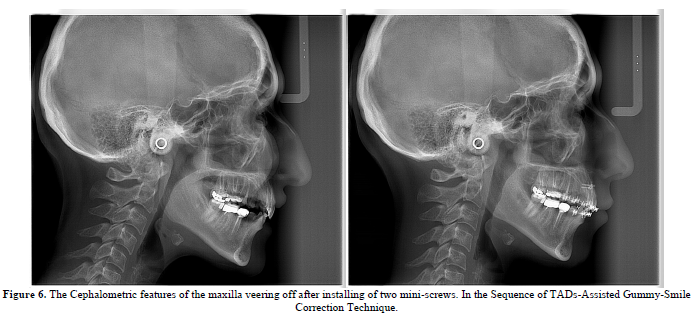

Hitherto, the cephalometric and clinical outcomes support the aforementioned approach (Figure 6).

Nonetheless, the clinical aspects support the TADs wielded Gummy-Smile Corrections (Figure 7).

TADs are quintessentially helpful in Gummy Smile Treatments, however, it’s recommended that the practitioner get the lowdown on where & when to apply (Figure 8).